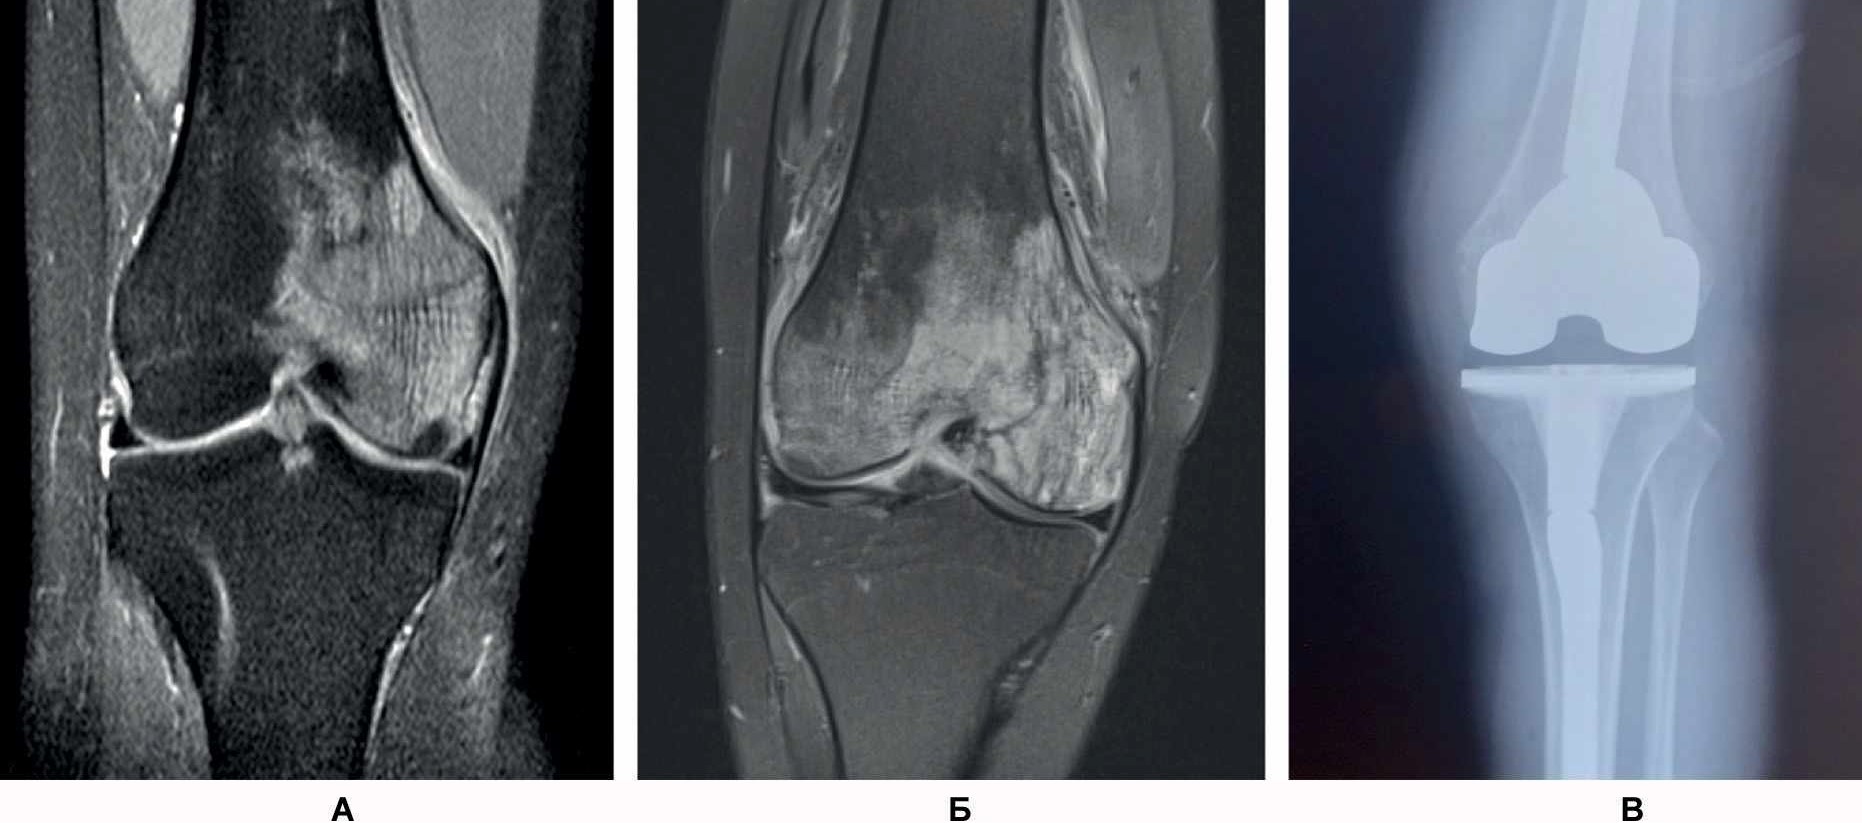

- Женщина А., 27 лет. При обращении жалобы на распирающую, пульсирующую боль в области медиального мыщелка левой бедренной кости и ночную боль (интенсивность – 7 баллов по визуально-аналоговой шкале боли, ВАШ) в левой ноге. Отмечается нарушение опороспособности на левую нижнюю конечность. Соматический и наследственный анамнез не отягощен. В мае 2021 г. перенесла острую респираторную вирусную инфекцию в легкой форме. 06.10.2021 г. выполнена спиральная компьютерная томография (СКТ) левого коленного сустава, обнаружен асептический некроз медиального мыщелка левой бедренной кости (рис. 1А). 25.11.2021 г. выполнены артроскопия левого коленного сустава, декомпрессия очага некроза. Назначено консервативное лечение. 16.01.2022 г. проведена контрольная МРТ – асептический некроз медиального мыщелка левой бедренной кости (см. рис. 1Б).

Рис. 1. СКТ левого коленного сустава у пациентки А. Диагноз: асептический некроз медиального мыщелка левой бедренной кости: 06.10.2021 г. (А), 25.11.2021 г. (Б), эндопротез левого коленного сустава (В).

На контрольном осмотре пациентка отмечает постоянную боль тянущего характера по медиальной поверхности левого коленного сустава, резкую боль (7 баллов по ВАШ) в области медиального мыщелка левой бедренной кости при попытке активного и пассивного сгибания коленного сустава и в области медиального мыщелка левой бедренной кости при осевой нагрузке на левую нижнюю конечность. Отсутствуют улучшения по данным МРТ, увеличивается функциональная недостаточность по клиническим данным.

11.02.2022 г. выполнена имплантация эндопротеза левого коленного сустава с одновременной реконструкцией биологической оси конечности (см. рис. 1В). В послеоперационном периоде на 7-е сутки пациентка отмечает восстановление функции коленного сустава, отсутствие болевого синдрома (1 балл по ВАШ).